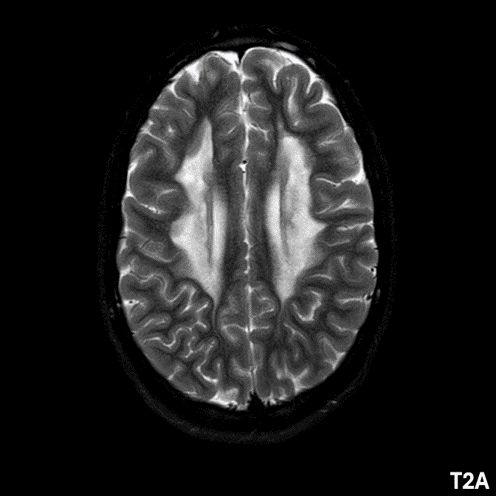

- A) Aksiyel T2A ve koronal T2A sekanslarda sentrum semiovale, korona radiata ve bazal ganglionlar düzeyinde bilateral frontoparietal derin periventriküler beyaz cevherde birleşme eğilimi gösteren hiperintens gliotik sinyal değişiklikleri (oklar) ve aksiyel T2A serilerde servikal spinal kordda posterior kolonda, lateral kesimlerde sinyal artımları (oklar) izlendi.

- LBSL, karakteristik radyolojik özelliklere sahiptir. MRG’de tipik olarak bilateral ve simetrik beyaz cevher sinyal değişiklikleri görülürken, subkortikal U lifleri, internal kapsülün posterior kolları, trigeminal sinir traktları, serebellum, korpus kallozumun spleniumu, medulla oblongata ve omurilikteki dorsal kolonlar ile lateral kortikospinal traktlar genellikle korunur.

- Etkilenen bölgelerde T1’de hipointens, T2/FLAIR’da hiperintens sinyal değişiklikleri izlenir. DWI’de lezyonların periferinde kısıtlı difüzyon görülebilir. MRS’de beyaz cevherde laktat artışı saptanabilir, ancak bu her hastada mevcut değildir.

- LBSL tanısında majör kriterler; subkortikal U lifleri korunmuş serebral beyaz cevher, servikal düzey dahil omurilik dorsal kolonları ve lateral kortikospinal traktlar, medulla oblongata piramitleri veya medial lemniskus dekusasyonu tutulumu iken; minör kriterler korpus kallozum spleniumu, internal kapsül posterior kolu, superior ve inferior serebellar pedinküller, trigeminal sinir traktları, mezensefalik trigeminal yollar, medulla oblongata anterior spinosebellar traktları ve serebellar beyaz cevherdeki sinyal değişiklikleridir.